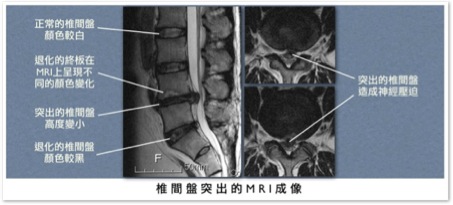

X光照相除了可能看到椎間距離減小或輕微的脊椎退化之外,因看不到椎間盤,並不能作為確診的依據。電腦斷層掃描

(computed tomography, CT) 或核磁共振造影 (magnetic resonance imaging, MRI)

才可清楚看到突出的椎間盤,並評估神經根受壓迫的程度。兩種檢查各有優缺點,孰優孰劣在文獻上尚未有定論,雖然各國學者都同意能同時有兩種檢查的影像分析是最好的選擇(美、日、韓等國都是如此),但在本國有礙於中央健保局的規範,兩者只能擇一進行;本人較偏好核磁共振造影,因其對脊椎內腫瘤、膿瘍等嚴重疾病的鑑別率遠較電腦斷層高。